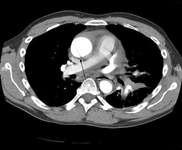

CT scan showing dissecting aneurysm in a 45-year-old patient with Marfan syndrome experiencing chest pain

Sanyal K, Sabanathan K. Chest pain in Marfan syndrome. BMJ Case Reports 2009; doi:10.1136/bcr.07.2008.0431